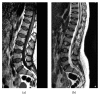

Pregnancy- and lactation-associated osteoporosis (PLO) is a rare form of osteoporosis. It results in severe low back pain in the last trimester of pregnancy and in the postpartum period, decreases in height, and fragility fractures, particularly in the vertebra. The current case report presents a 32-year-old patient who presented with back and low back pain that began in the last trimester of the pregnancy and worsened at two months postpartum and who was diagnosed with pregnancy- and lactation-associated osteoporosis after exclusion of other causes; the findings are discussed in view of the current literature. PLO is a rare clinical condition causing significant disability. PLO must be kept in mind in the differential diagnosis in patients presenting with low back pain during or after pregnancy. The patients must be evaluated for the risk factors of PLO, and an appropriate therapy must be initiated.